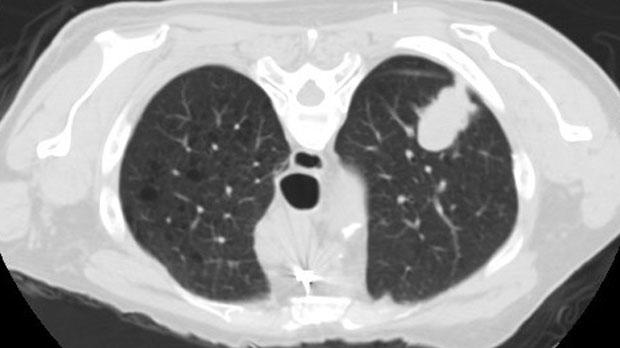

Lung Cancer Detection Using Low-Dose CT | CitiScan Radiology Brisbane

Lung Cancer Detection Using Low-Dose CT | CitiScan Radiology Brisbane www.citiscan.com.au